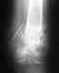

Двулодыжечный перелом со смещением и подвывихом кнаружи.

Через 4 часа после перелома была сделана репозиция и наложен циркулярный гипс. Сегодня 10 дней со дня репозиции, опухоль спала, гипс болтается, натерла мозоль под гипсом. Надо ли перекладывать гипс, или терпеть и ждать 21 день (как говорит лечащий доктор). И еще - на снимке идеально поставили внешнюю лодыжку, а у внутренней отломан нижний край и на снимке расстояние между обломками где то 1 мм, нужно ли делать штырь или есть шанс, что все и так срастется? Снимок прилагаю